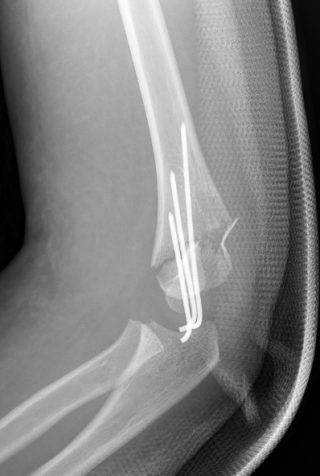

3、小林(化名):男、4岁、在家里从双层床上摔下致左肘部肿痛、畸形、活动受限4小时就诊我院。(下图为患儿术前X线片)

麻醉下手法整复经皮钢针内固定,术后患儿恢复良好。(下图为患儿术后X线片)